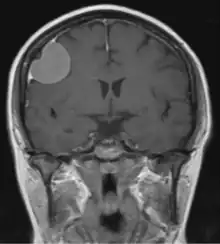

Dural tail sign

The dural tail sign (also known as "dural thickening", "flare sign", or "meningeal sign") is a radiological finding observed in magnetic resonance imaging (MRI) studies of the brain that refers to a thickening of the dura mater immediately adjacent to a mass lesion, such as a brain tumor.[1] Initially, the dural tail sign was thought to be pathognomonic of meningioma, a slow-growing tumor that arises from the meninges.[1] However, subsequent studies have shown that it can also be observed in various intra- and extra-cranial pathologies and in spinal lesions.[1] It is not a completely sensitive finding, as it is seen in only 60-72% of cases.[2] It is not completely specific either, as it has been described associated with lesions like neuromas, chloromas, pituitary diseases, granulomatous disorders, cerebral Erdheim-Chester disease, lymphomas, metastasis, hemangiopericytomas, schwannomas, and gliomas such as glioblastoma multiforme (GBM).[2][3] The final diagnosis should be further established through cerebrospinal fluid analysis or histopathological examination following a biopsy.[3]